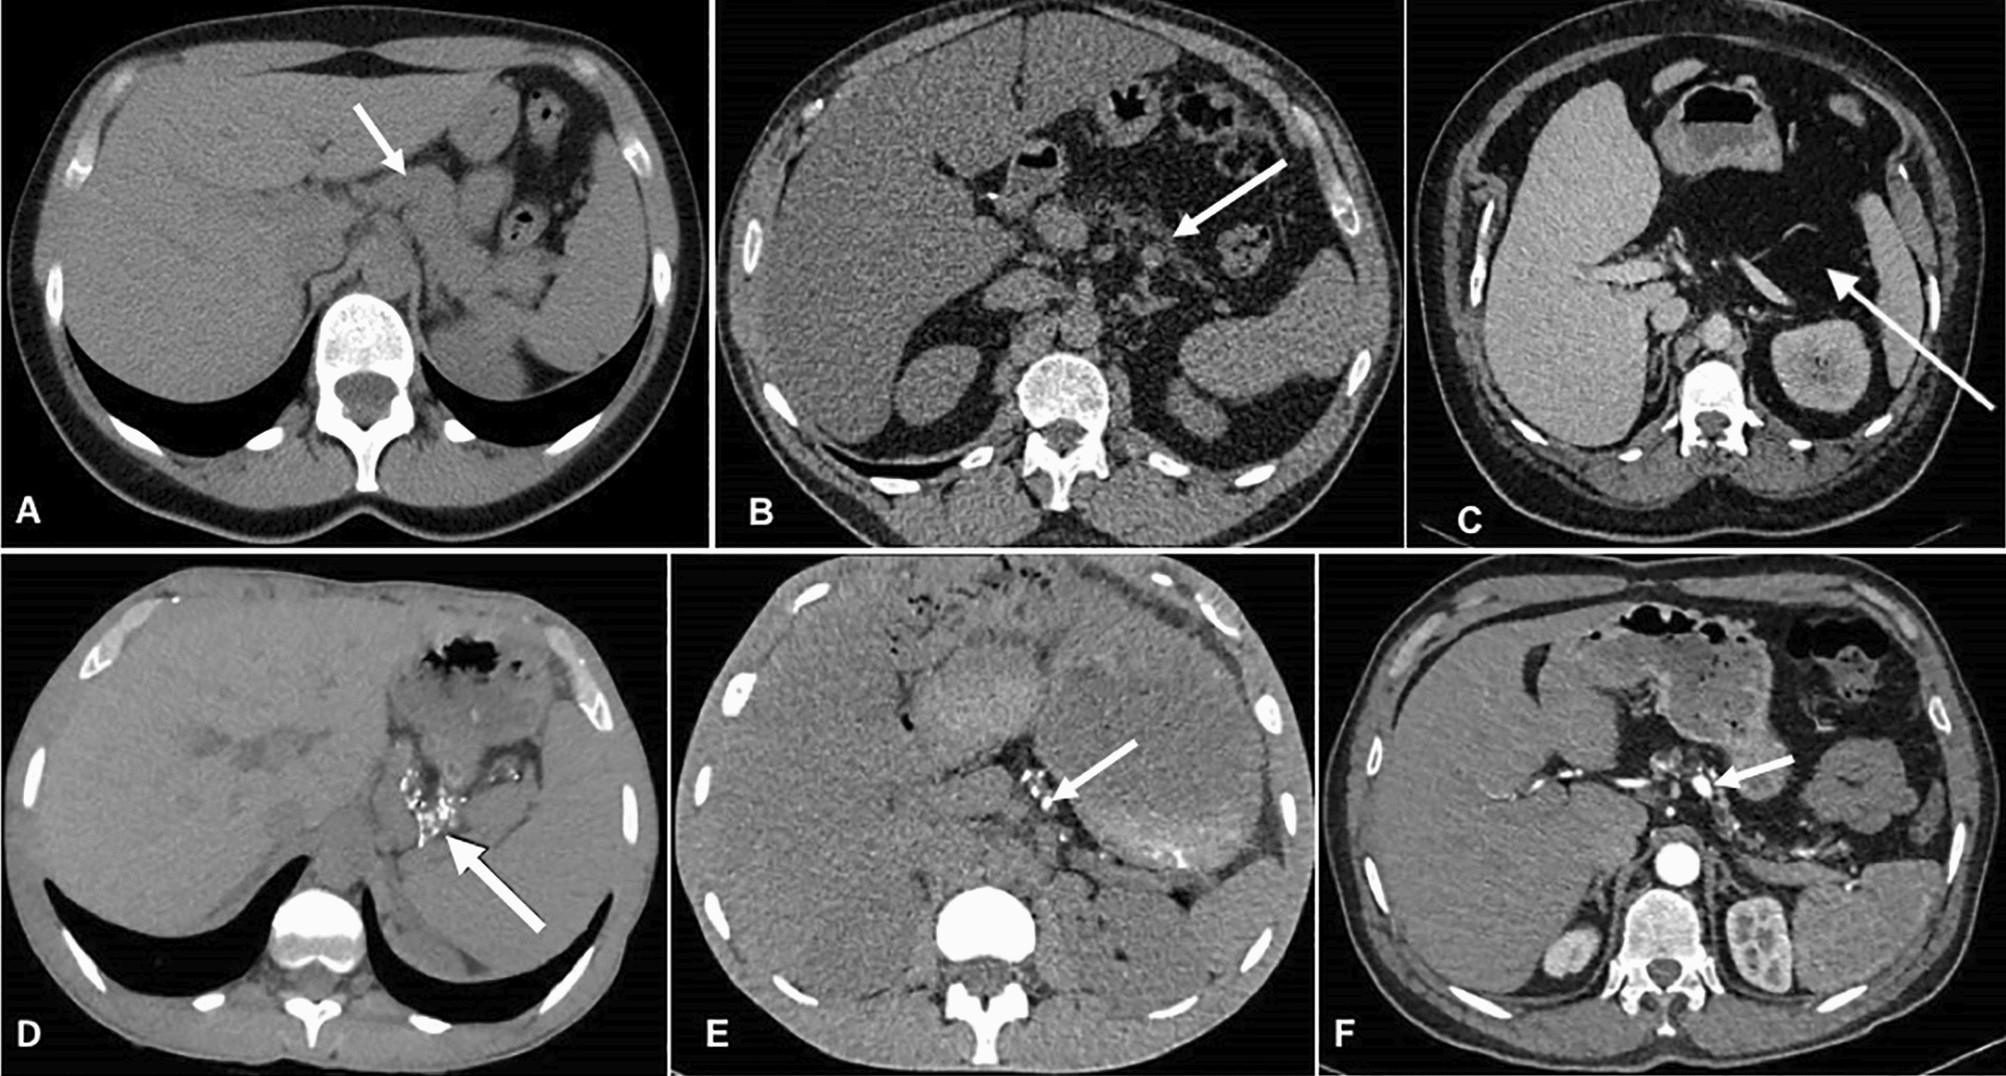

Figure 2

Computed tomography without contrast Top row: Different degrees of pancreas lipomatosis. (a) Normal pancreas (b) Partial lipomatosis of the pancreas. (c) Complete lipomatosis of the pancreas (white arrow shows the visually empty pancreatic area.) Bottom row (d–f): three examples of pancreatic calcifications (arrows). Of note, all images of bottom row show partial lipomatosis of the pancreas.